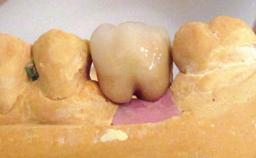

A 65-year-old female patient was referred to the periodontist for assessment and management of implant site 12. Implant 12 had been placed ten years previously and restored with a cemented single crown. The patient was a non-smoker in good general and periodontal health. On examination there were 7 mm probing depths at implant 12 with suppuration and bleeding on probing. The patient was aware of the presence of pus but had no discomfort. A periapical radiograph showed marginal bone loss to approximately the third thread of the implant. Previous radiographs obtained from the referring clinician indicated that there had been progressive bone loss since the implant was restored. A diagnosis of periimplantitis was made.